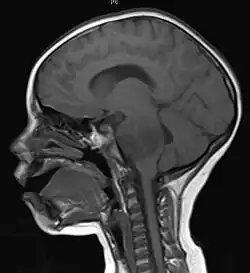

Anatomy